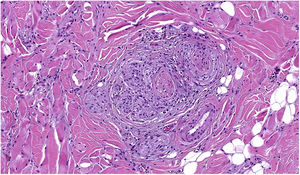

TILs should be classified as absent (not identified or identified but not in contact with the tumor), brisk (infiltration of the entire base of the tumor [Fig. 1) or diffuse infiltration of the tumor) (Fig. 2), or nonbrisk (focal infiltration or infiltration of part of the base of the tumor).

The pathology report should also specify whether the infiltrate is intratumoral, peritumoral, or both.